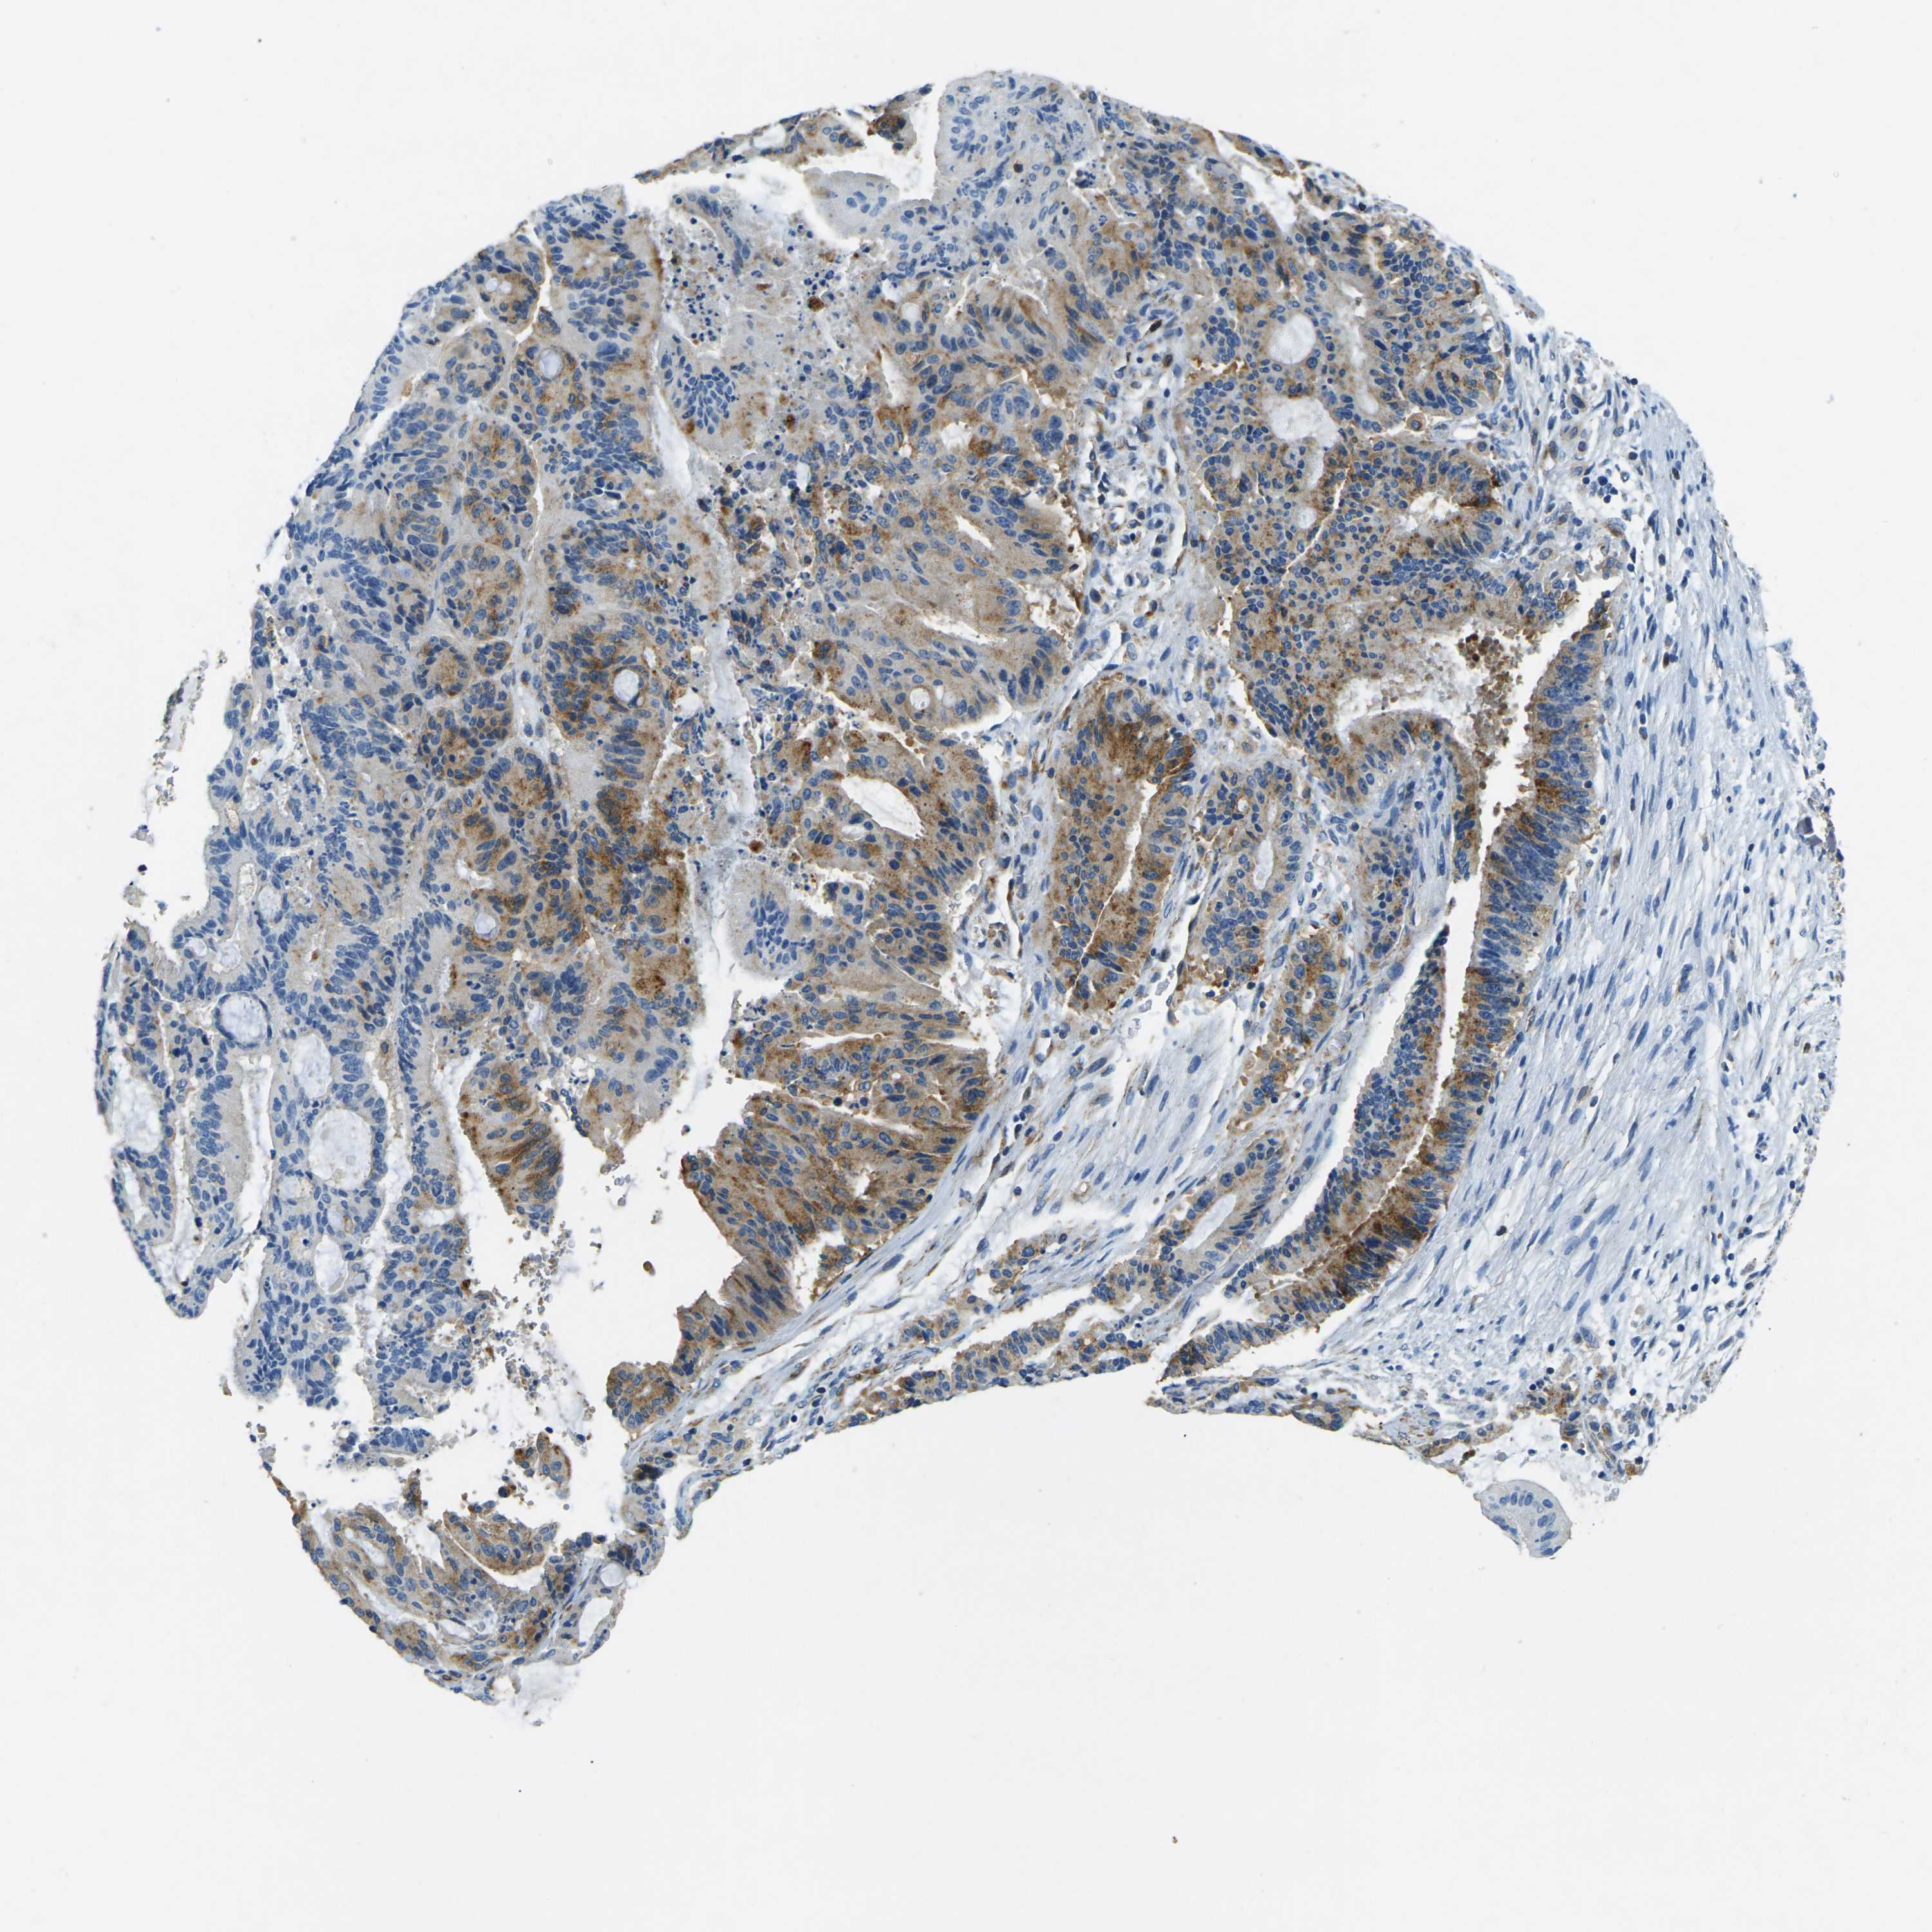

LIVER CANCER - Protein expressioni

A mouse-over function shows sample information and annotation data. Click on an image to view it in a full screen mode. Samples can be filtered based on level of antibody staining by selecting one or several of the following categories: high, medium, low and not detected. The assay and annotation is described here.

Note that samples used for immunohistochemistry by the Human Protein Atlas do not correspond to samples in the TCGA dataset.

Antibody stainingi

Antibody staining in the annotated cell types in the current human tissue is reported as not detected, low, medium, or high, based on conventional immunohistochemistry profiling in selected tissues. This score is based on the combination of the staining intensity and fraction of stained cells.

Each image is clickable and will lead to virtual microscopy that enables deeper exploration of all samples and also displays staining intensity scores, fraction scores and subcellular localization as well as patient and tissue information for each sample.

Antibody HPA006889

Antibody CAB011498

Staining

High

Medium

Low

Not detected

Intensity

Strong

Moderate

Weak

Negative

Quantity

>75%

75%-25%

<25%

None

Location

Nuclear

Cytoplasmic/membranous

Cytoplasmic/membranous,nuclear

Cholangiocarcinoma

Carcinoma, Hepatocellular, NOS